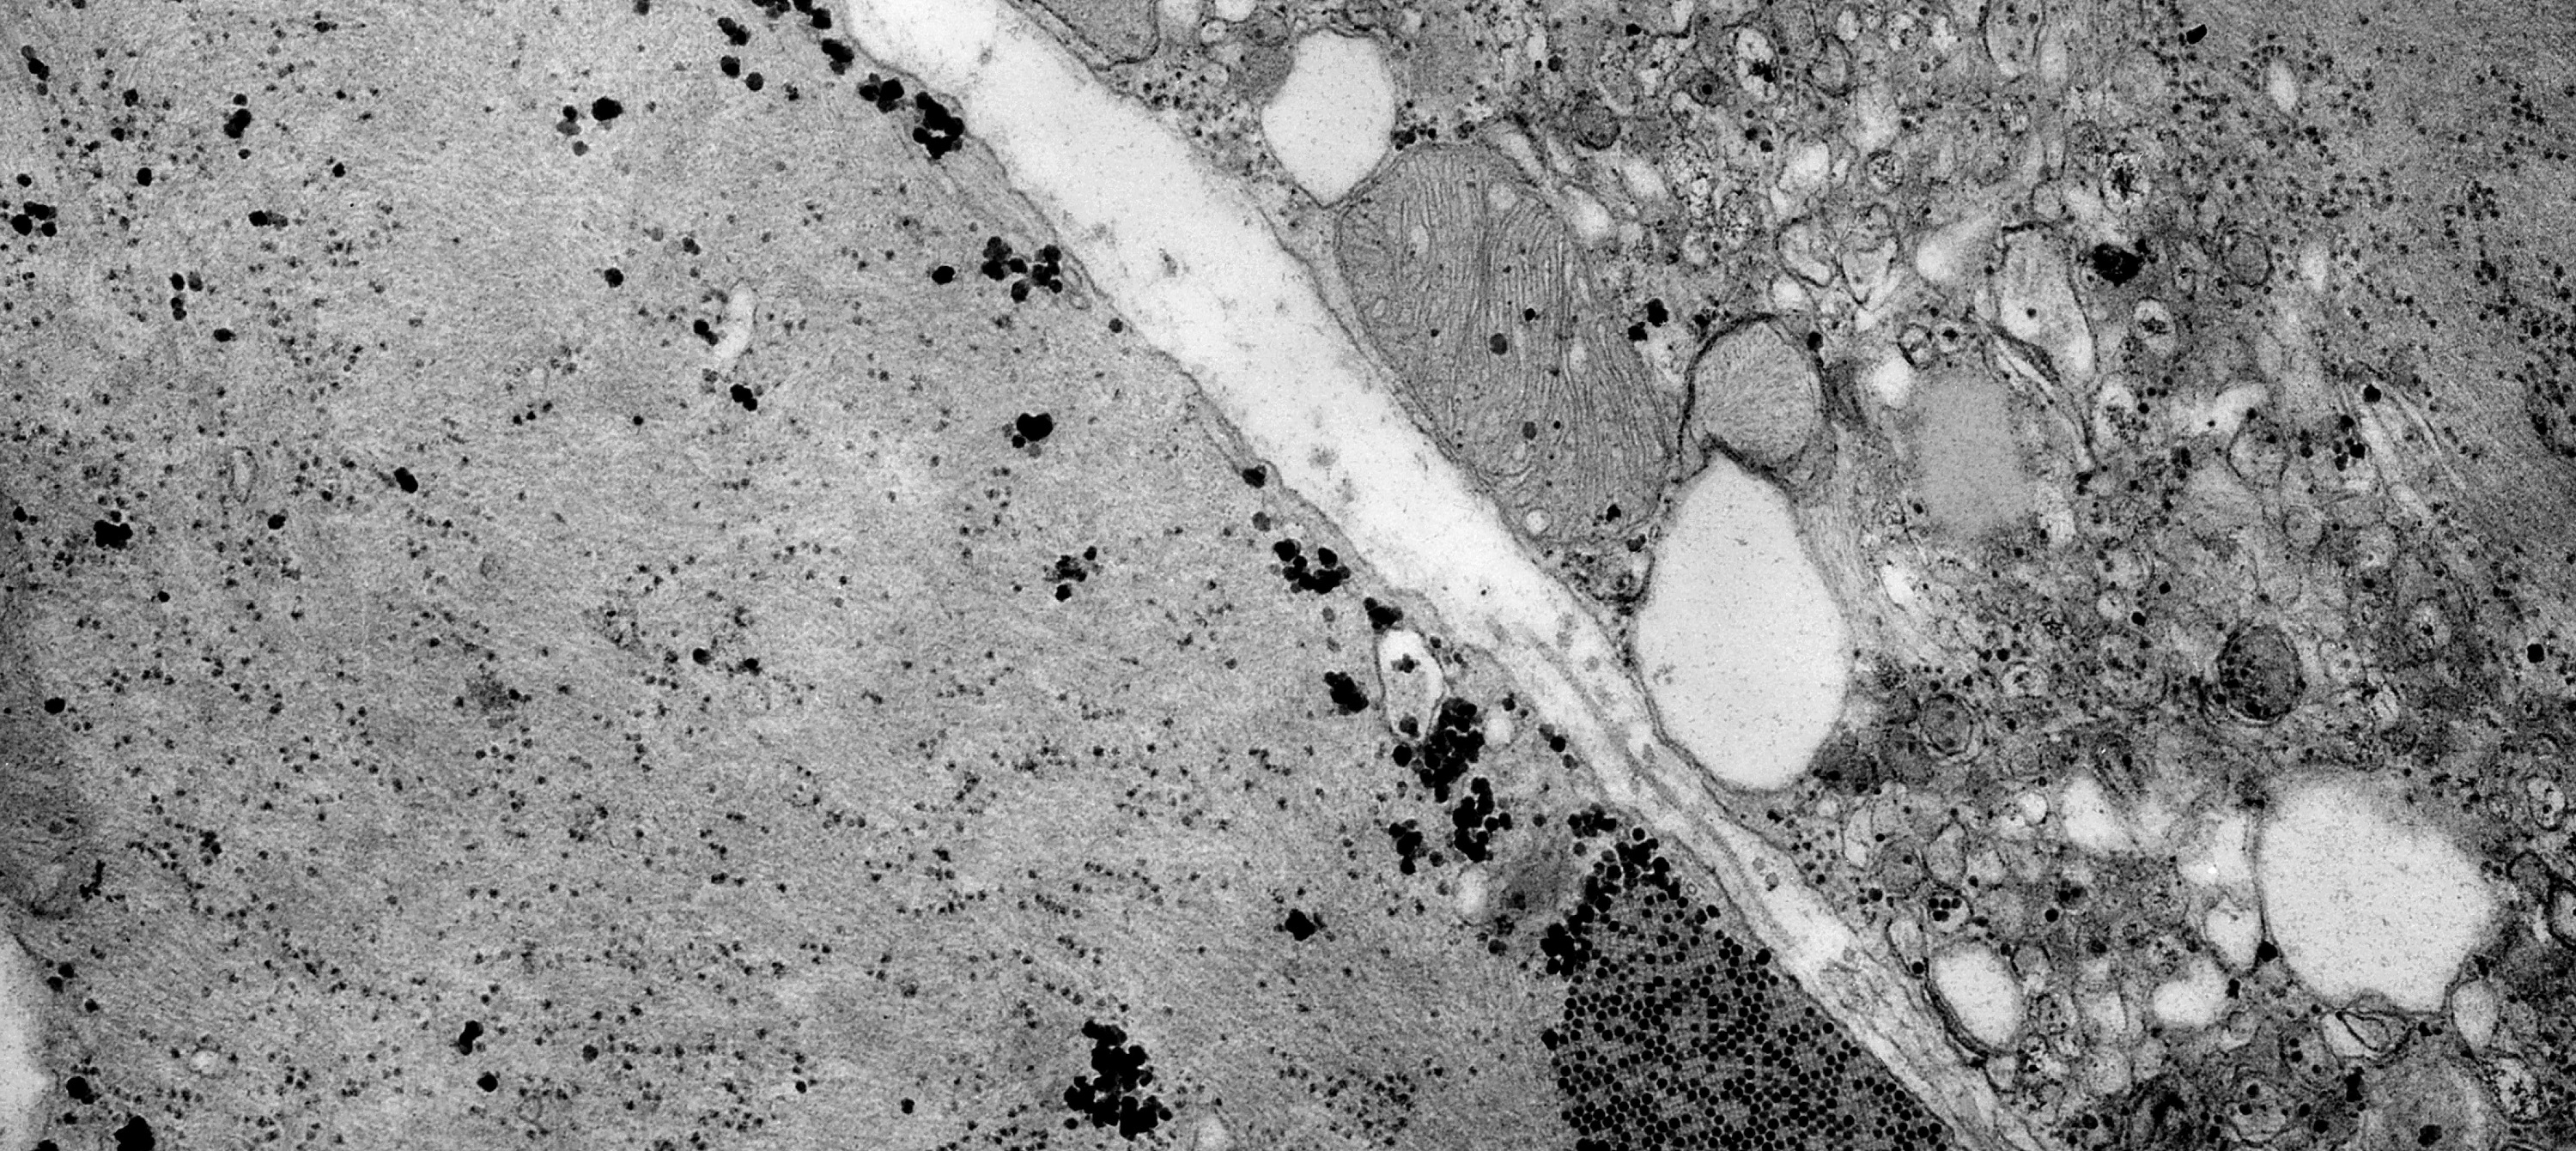

Descubren una nueva función de las proteínas SOS que altera la dinámica y el metabolismo de las mitocondrias